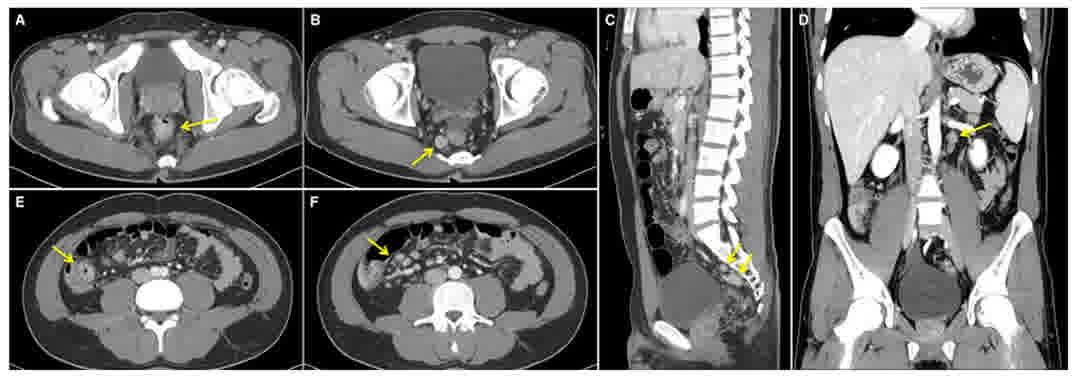

The most probable diagnosis was a rectal carcinoid tumor combined with acute gastroenteritis, and it was decided to pursue a histopathological diagnosis by endoscopic or surgical resection following resolution of the acute enteritis. Prior to resection, an abdominopelvic computed tomography (CT) scan performed to evaluate the distal rectal mass and terminal ileal inflammation; this indicated wall thickening of the terminal ileum with several mesenteric lymph nodes in the right lower quadrant, a 1.5-cm nodule in the distal rectum with an enlarged lymph node in the right posterior mesorectum, and several enlarged nodes along the inferior rectal vessel and left para-aortic area (Fig. 3).

Figure 3.

Abdominopelvic computed tomography scan indicating multiple enlarged lymph nodes. (A) 1.5-cm nodule in the distal rectum (arrow). (B) Enlarged lymph node in the right posterior mesorectum (arrow). (C) Arrows indicate several aggregated enlarged lymph nodes along the inferior rectal vessel. (D) Left para-aortic lymph node enlargement (arrow). Wall thickening of the (E) terminal ileum, with (F) several enlarged mesenteric lymph nodes in the right lower quadrant.